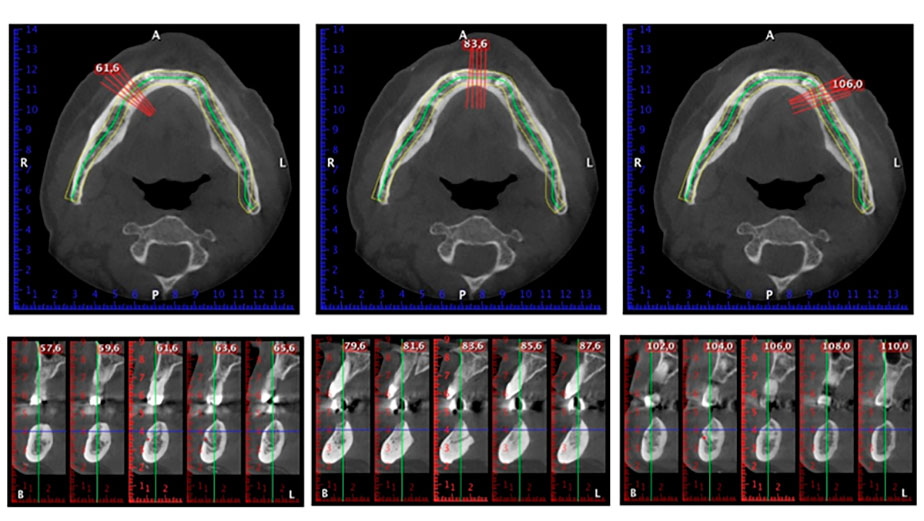

A three-dimensional cone beam computed tomography scan (CBCT, Planmeca) was performed to aid planning and minimize risks. This revealed that the quality and quantity of the available bone were sufficient for the surgery and immediate restoration using the Fast & Fixed method. Following the protocol for this concept, the implants are inserted at 35, 32, 42 and 45. Angling the distal implants by up to 45° shifts the emergence profile to posterior and generates a larger support polygon (Fig. 3).